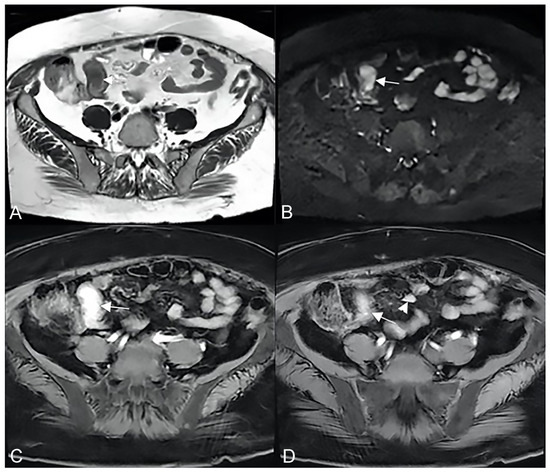

Figure 3.

Active inflammatory Crohn’s disease with layered hyper-enhancement pattern (A–D): the presence of active Crohn’s disease is indicated by small bowel wall thickening with layered hyperenhancement on coronal fat-suppressed contrast-Enhanced T1-Weighted MRE images. Active inflammatory Crohn’s disease with homogeneous enhancement pattern (E,F): the presence of active Crohn’s disease is indicated by small bowel wall thickening with homogeneous enhancement on coronal (E) and axial (F) fat-suppressed contrast-Enhanced T1-Weighted MRE images.